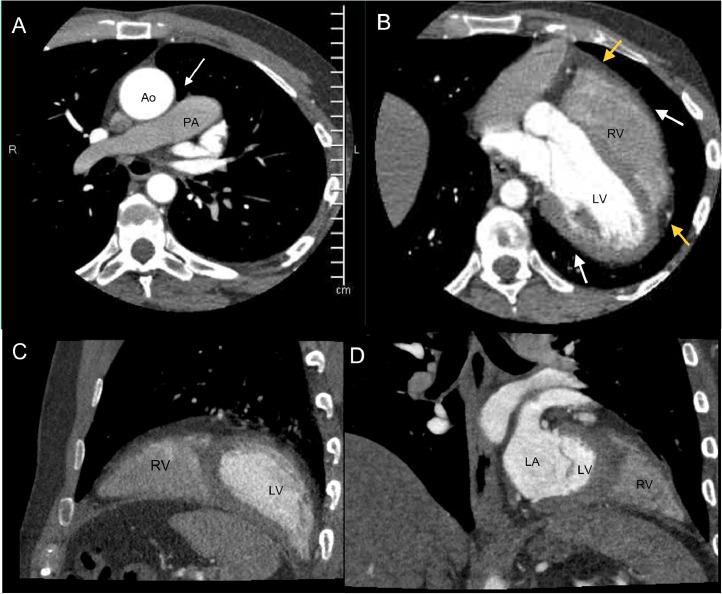

This case report describes a 40-year-old male who presented to the emergency department (ED) with chest pain. Initial diagnostic workup was concerning for a congenital cardiac anomaly, further imaging revealed complete congenital absence of the pericardium (CAP) which is a rare condition. Multimodality cardiac imaging including cardiac computed tomography angiogram (CCTA) was used to confirm the diagnosis of CAP. We briefly discuss various clinical presentations of CAP along with potential complications and other anomalies that could be associated with pericardial agenesis.

本病例报告描述了一名40岁男性,他因胸痛被送往急诊科。初步诊断检查怀疑有先天性心脏异常,进一步的影像学检查显示为完全性先天性心包缺如(CAP),这是一种罕见的病症。包括心脏计算机断层扫描血管造影(CCTA)在内的多模态心脏成像用于确诊CAP。我们简要讨论了CAP的各种临床表现以及可能与心包发育不全相关的潜在并发症和其他异常情况。